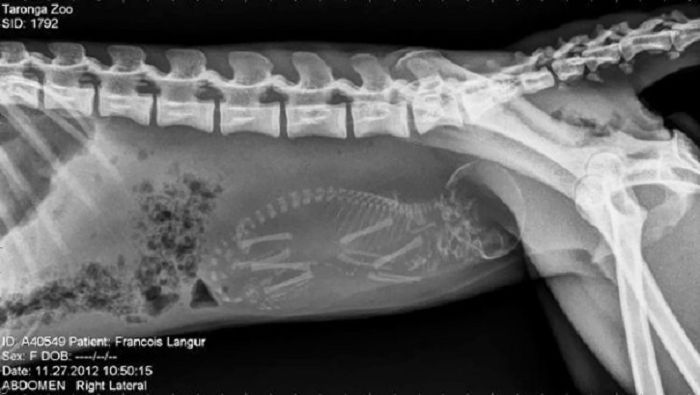

以下就是一些动物在怀孕时的X光片。

2. 黑叶猴